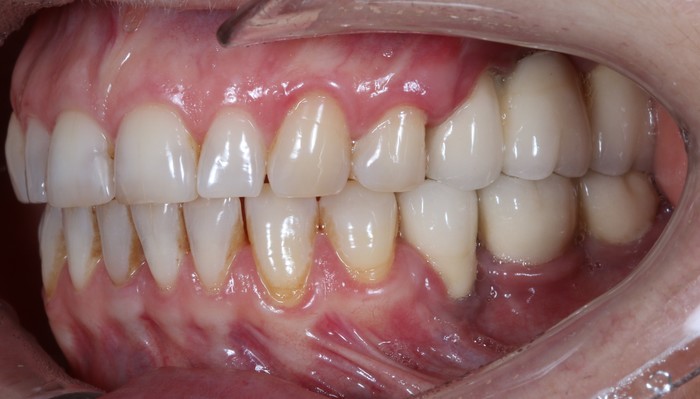

Интересно ли вам на сколько «попал» пациент только лишь потому, что не соблюдал элементарных вещей и забил на дальнейшее восстановление зубов? Так вот, около 500К. Это сумма выкинутых на помойку денег. Не говоря уже о том, что при повторном протезировании и исправлении сложившейся ситуации ценник будет выше, если не в два, то в полтора раза точно.

Поэтому я призываю вас - не пренебрегайте профилактическими осмотрами у стоматолога. Тем более, если у вас есть те или иные ортопедические конструкции. Этого пиздеца можно было легко избежать, если бы мужчина приходил на плановые приёмы, где доктор проводил бы ТО в виде снятия коронок, их чистки и, как не смешно это звучит, заново учил бы правильно ухаживать за зубами. (К слову - постоянное протезирование никак не умоляет необходимости в профилактических осмотрах)